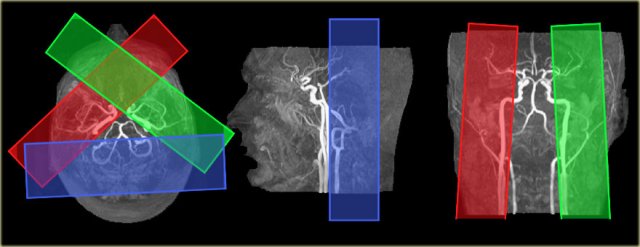

On the left the time-of-flight MR angiography-images of brain-feeding arteries showing the planning of the selective slabs for perfusion territory imaging of the left and right internal carotid artery and the vertebrobasilar artery.